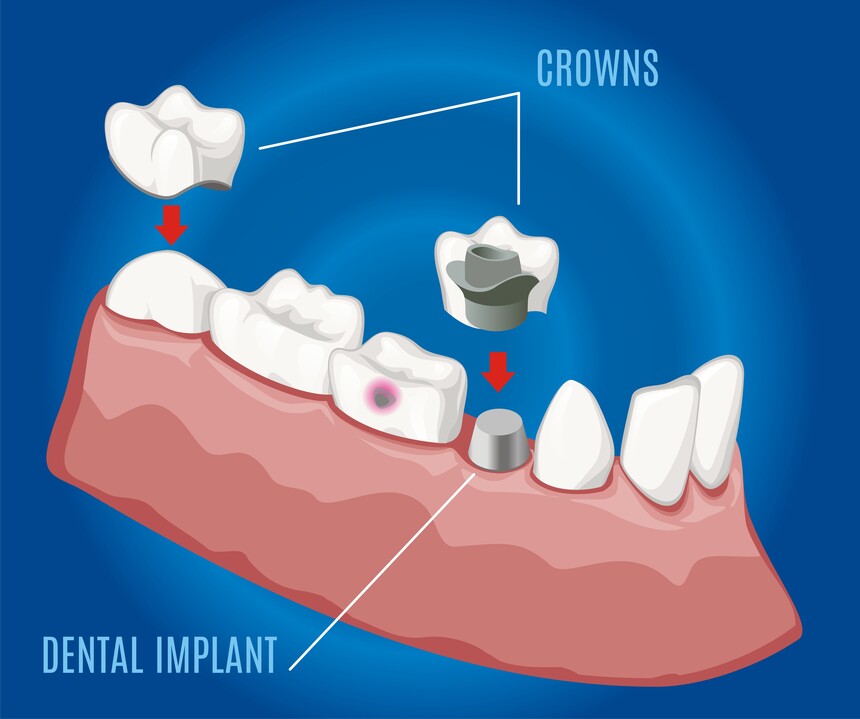

Crowns, Caps, Bridges & Dentures in College Road Nashik

reliable Crowns, Caps, Bridges & Dentures in College Road Nashik? Care 32 Dental & Implant Clinic offers top-tie...

Dental Implant in College Road Nashik | Care32 Dental Clinic

Dental implants have revolutionized modern dentistry, offering a permanent and effective solution for missing teeth. If ...

Dental Implant in Canada Corner Nashik | Care32 Dental Clinic

A confident smile plays a crucial role in our self-esteem and overall well-being. However, missing teeth can lead to ora...

Crowns, Caps, Bridges & Dentures in Canada Corner Nashik

A healthy and confident smile plays a crucial role in one's self-esteem and overall well-being. However, missing or dama...